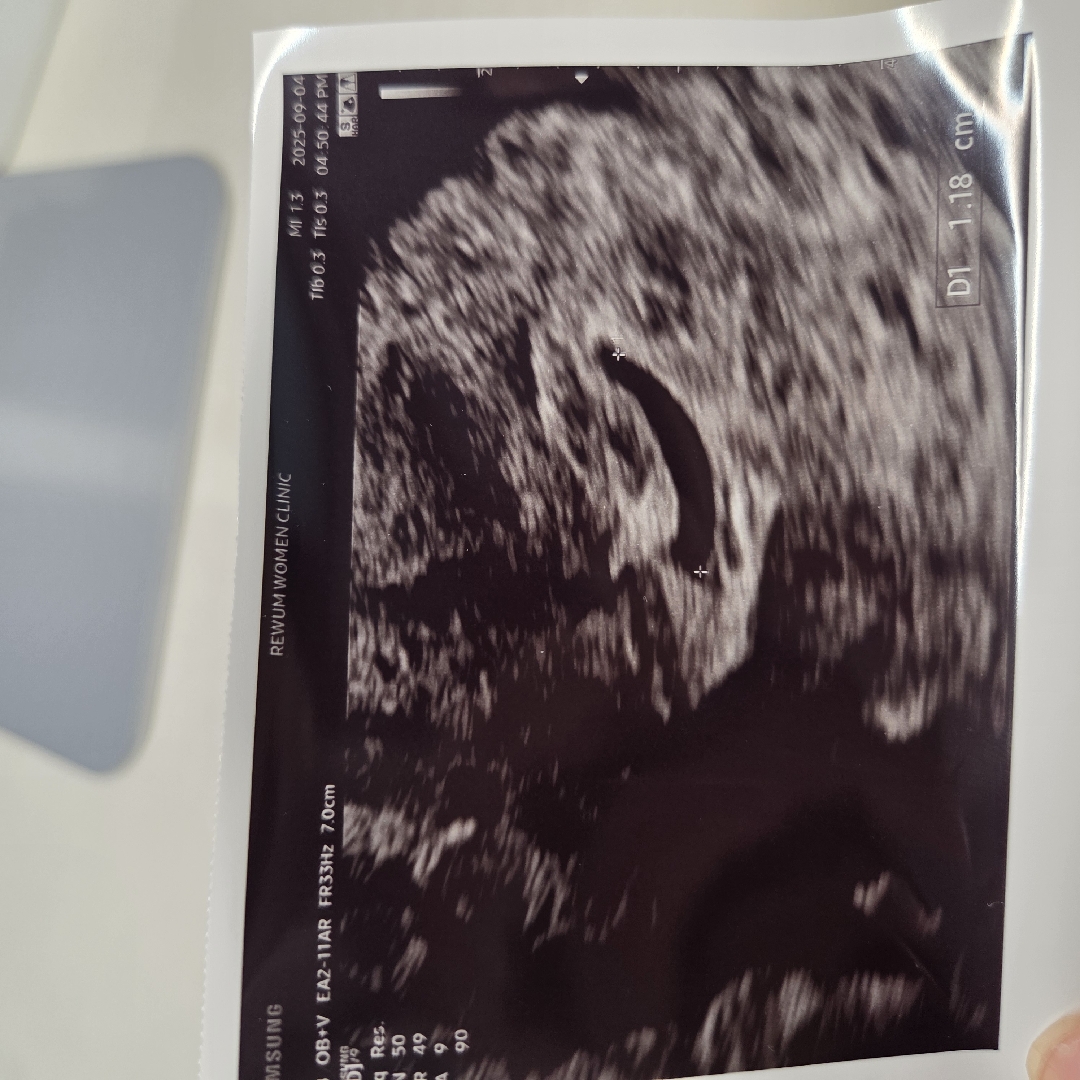

월요일에 아기집0.35cm, 피검사수치1200정도 나왔고 오늘 다시 병원가니 아기집 1.18cm, 피검사수치 5400정도 나왔다네요. 근데 아기집이 피고임에 눌려서 모양이 안 좋고 유산기가 있다고 질정7일 처방해주셨어요. 최대한 누워서 생활하면 괜찮아진다고 하는데.. 유산기가 있다는 말이 너무 무서워요..😭 분홍색 작은 덩어리가 소변볼때 1~2개 떨어지는 정도인데 정말 누워서 생활하면 괜찮아질까요? 눈물도 자꾸나고 무서워요..